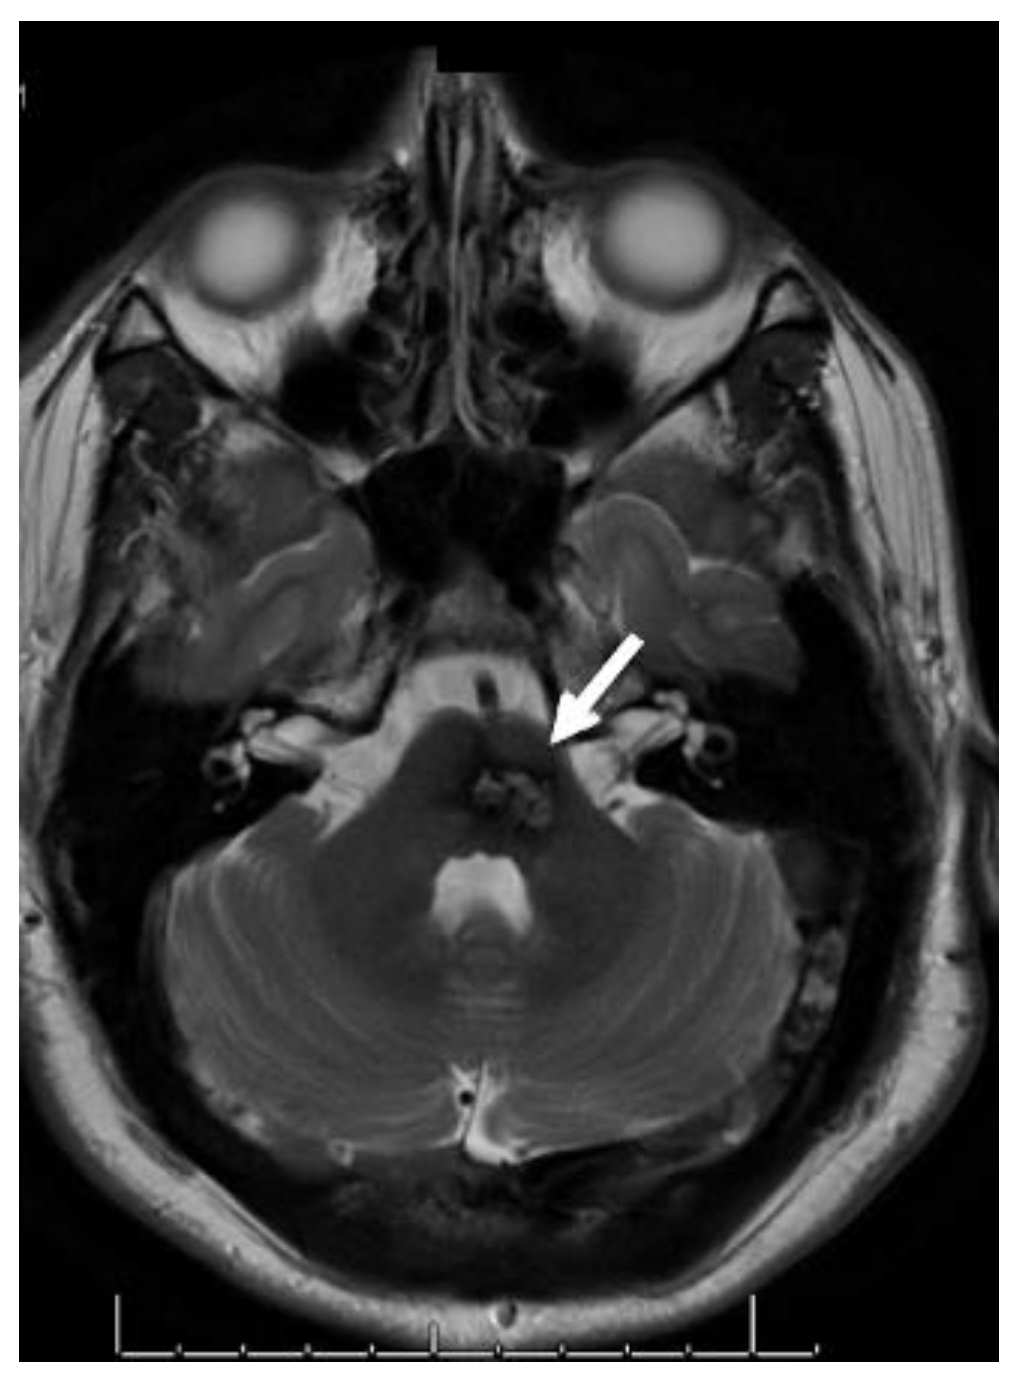

7. Management of Symptomatic Infratentorial Cavernomas